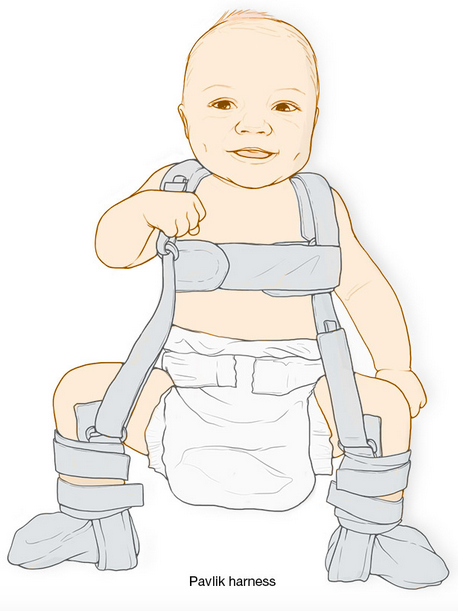

5. Babas wat gebore word met ‘n heupgewrig wat maklik uit die potjie kan glip, word in ‘n ‘padda’-spalkie geplaas sodat die heuppotjie reg kan ontwikkel om die kop van die bobeen in die potjie te anker.